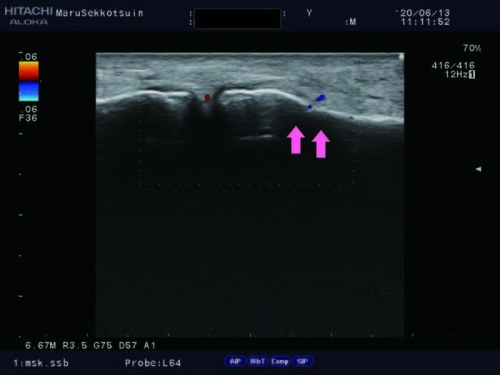

靴を履こうと踵に指を刺した時に「尺測手根屈筋の肉離れ」

尺側手根屈筋肉離れ.jpg